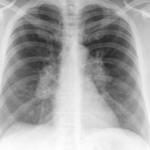

Signs

Album: Signs

Date: 04/28/2014

Size: 29 items

Views: 66515